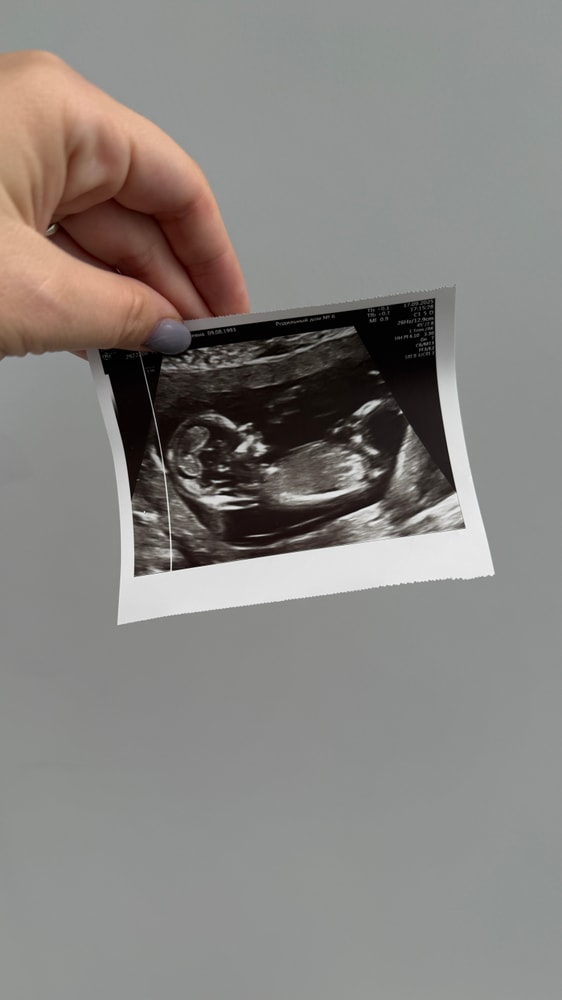

Первый скрининг.

УЗИ, КТГ, доплерСходили вчера на скрининг. Все хорошо 🤗

на узи уже было видно, что спим мы как папа) с рукой на глазках)) так это мило) на таких маленьких сроках замечать привычки родителей)

поставили 13 недель и 2 дня. Идем на 4 дня впереди)